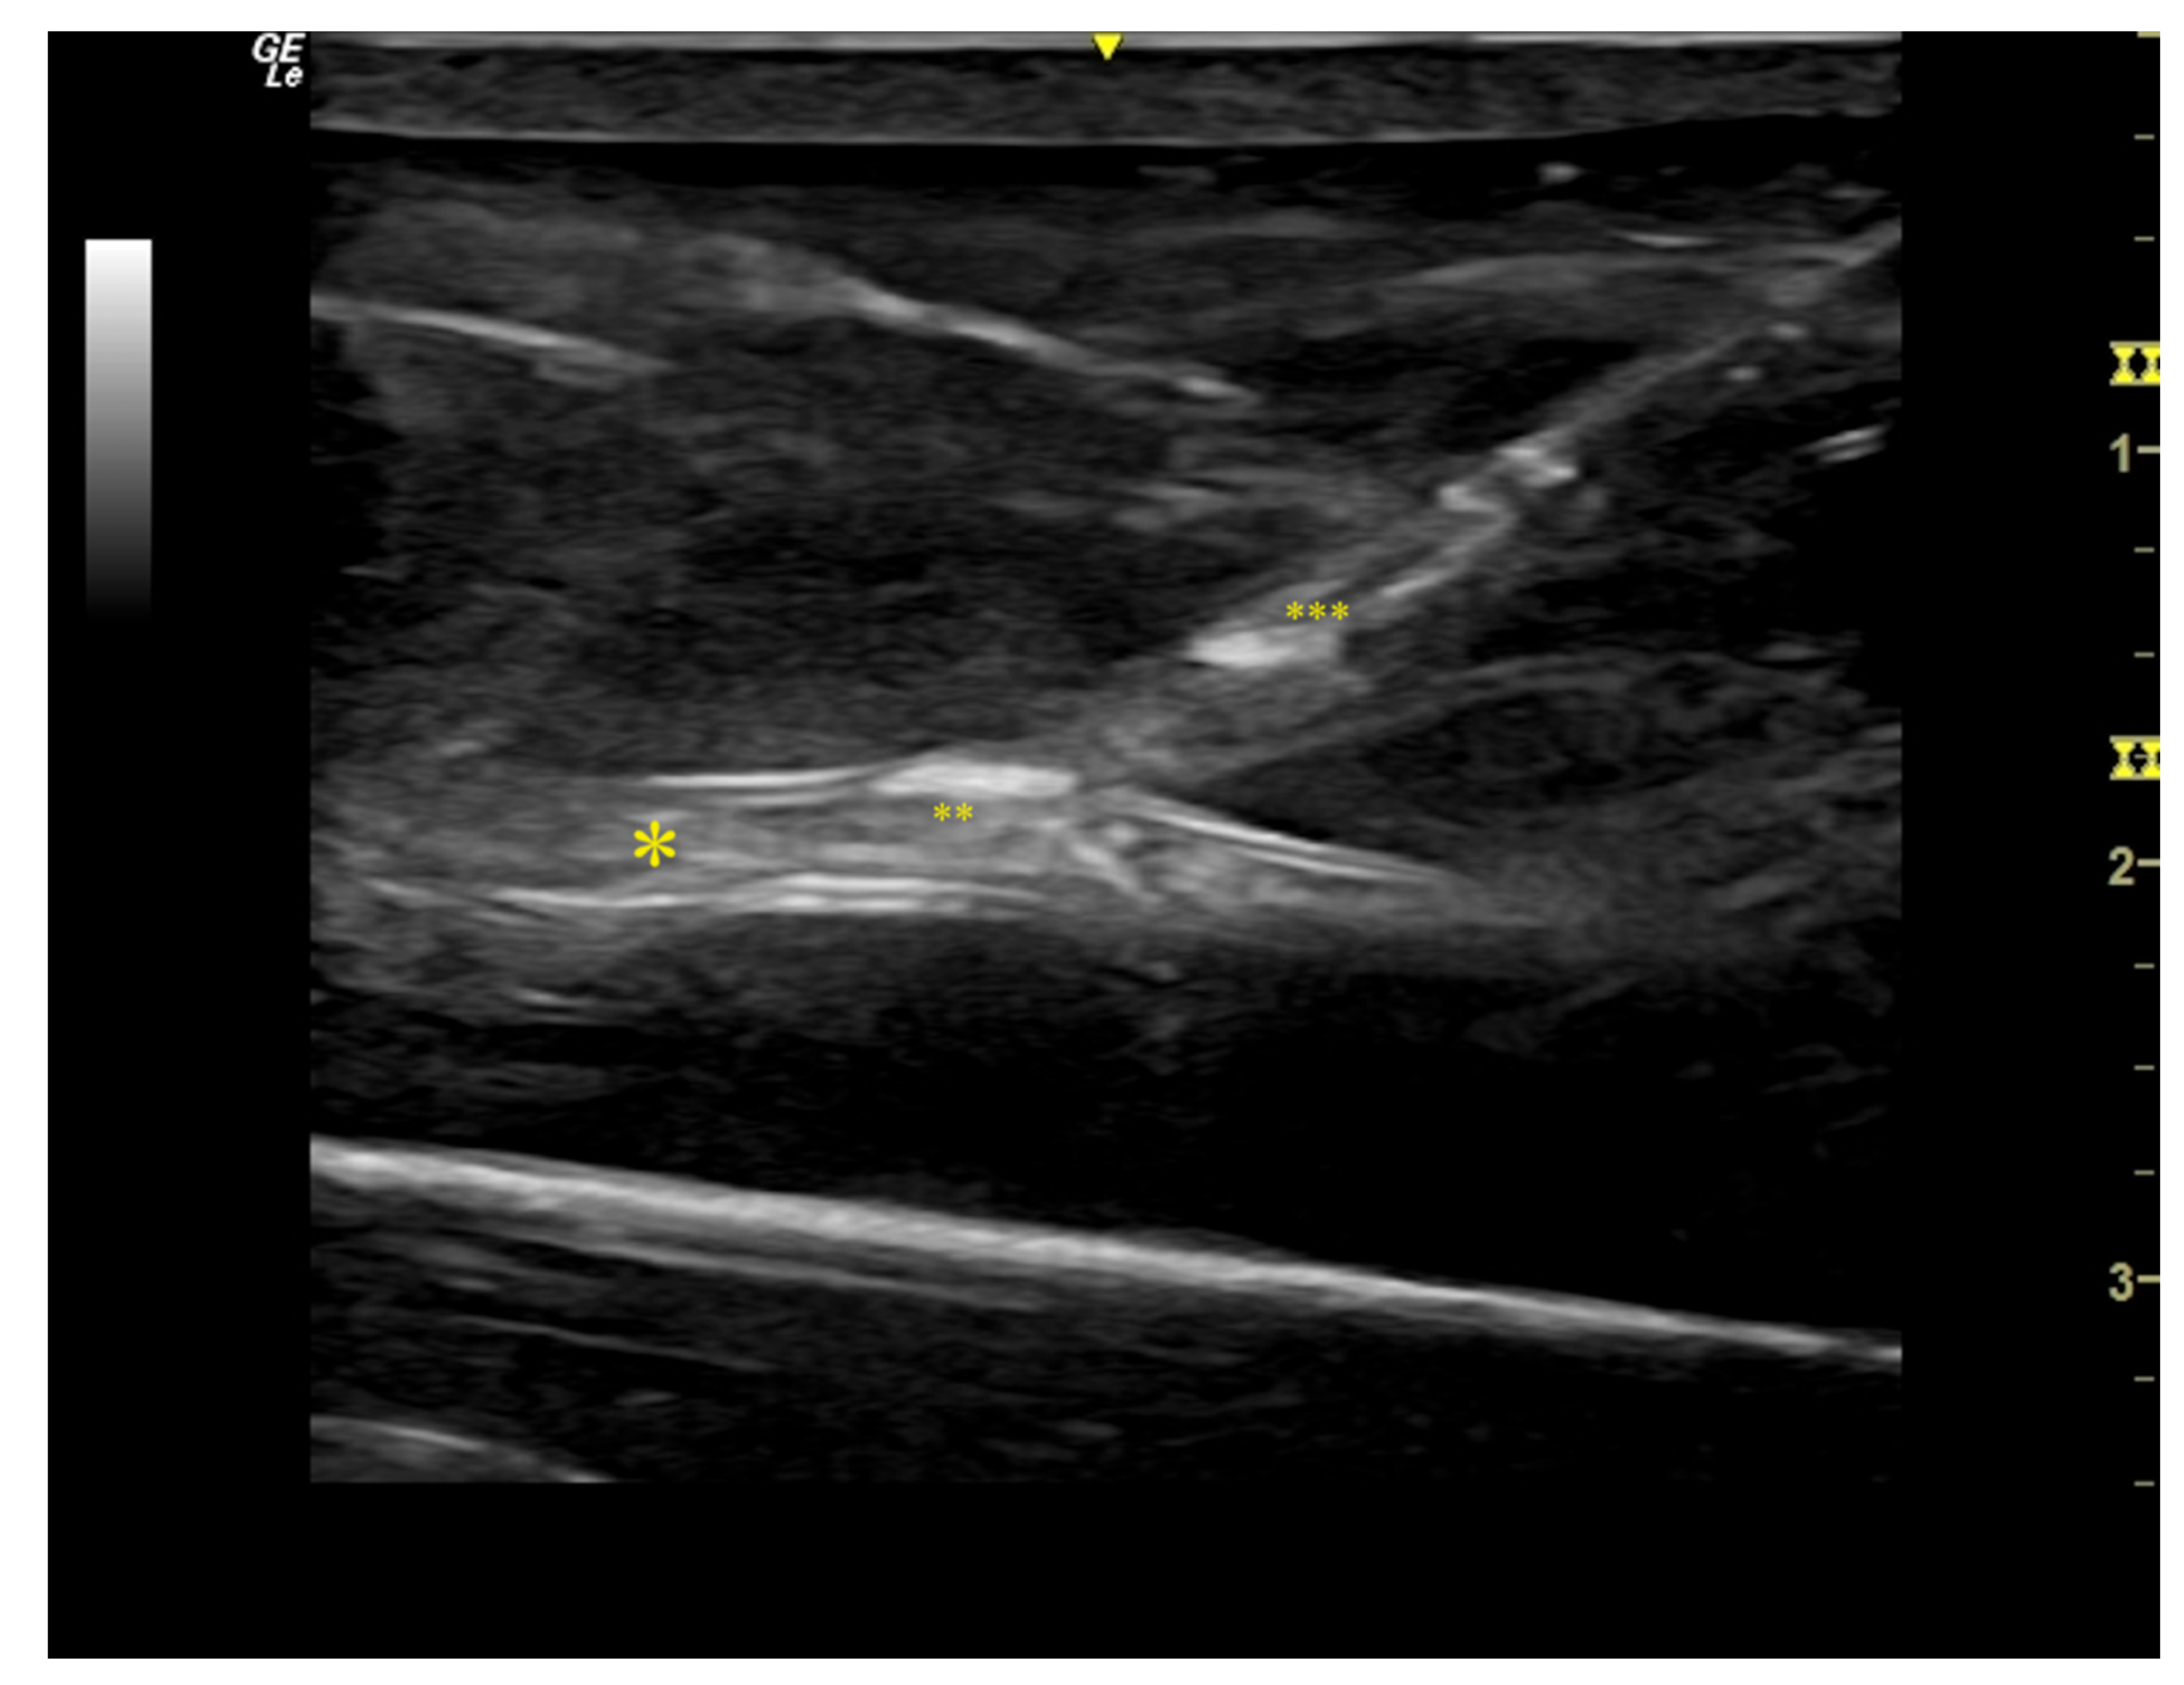

| Task type | Correct identification of DCV and PRA, diameter and distance measurement | Successful puncture of PRA through DCV | VUS-guided guide-wire advancement and sheath insertion | Correct placement of Ellipsys® catheter | Correct application of PTA balloon |